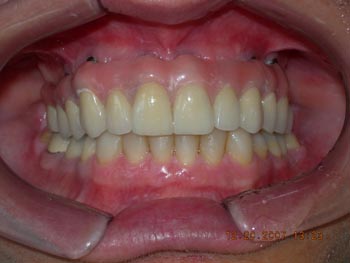

Vista frontal após correção ortodôntica e finalização da protocolo com dentes individuais em metalocerâmica

Resultado final